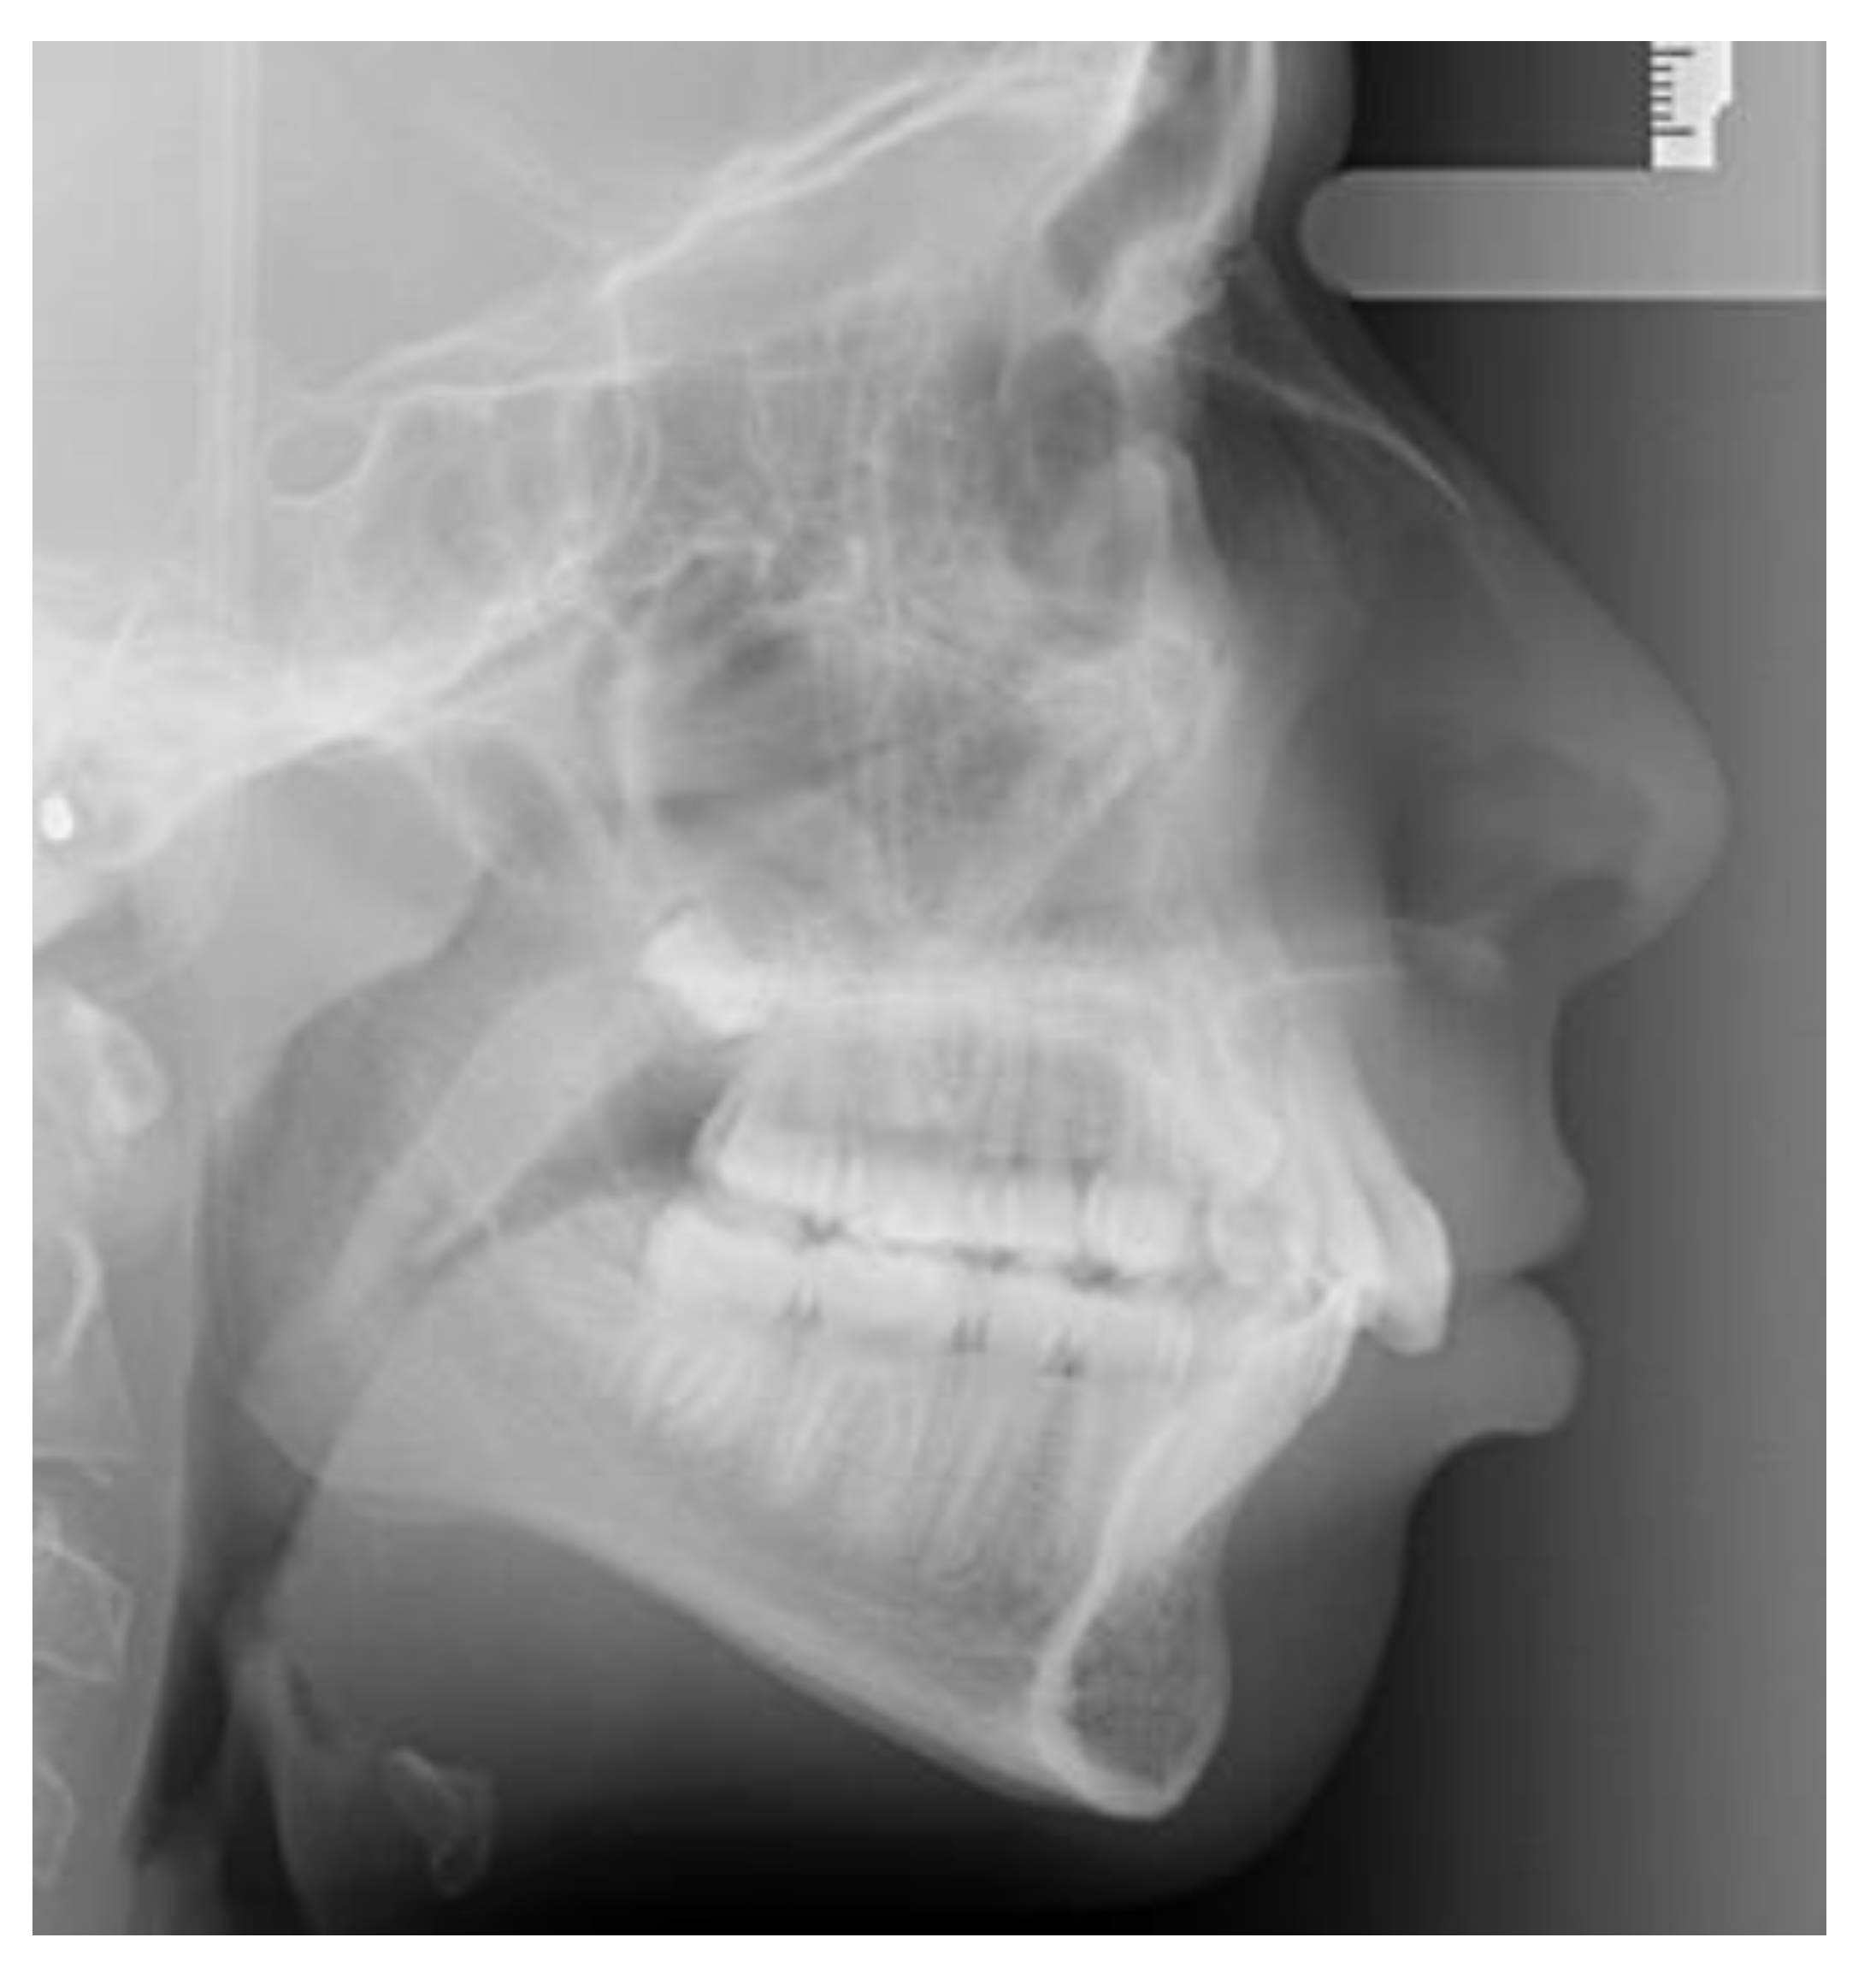

Lateral cephalometric radiographs were used to measure skeletal relationship angle (ANB) and evaluate PP (Figure 1), sella bridging (Figure 2) and atlas posterior arch deficiency (Figure 3).

Sella turcica bridging measurement was performed measuring interclinoidal distance (from the upper portion of sella tuberculum to the sella turcica dorsum) and the greatest distance/diameter between the tip of sella turcica tuberculum and the posterior sellae contour.

The standard scoring scale by Leonardi et al. [7] was used: the absence of bone calcification and sella bridging (type I), partial calcification (type II), complete calcification (type III).

Figure 2. Full sella bridging.